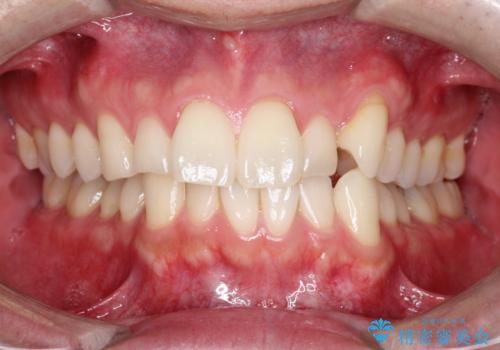

- 前歯の凸凹と顎の偏位を主訴に来院されました。

下顎の偏位を認めましたが、外科矯正を希望されなかったためできる範囲で顎の偏位を治すことができるよう治療を行なっております。

治療開始前に、下顎位の評価をおこなうことで、完成度の高い治療を行うことができました。